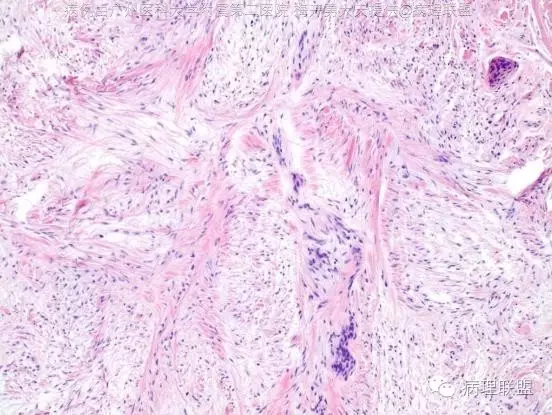

M/36,左足背肿物,直径1.5cm(病例由广州医科大学附属第二医院 梅开勇教授提供,致谢!)

镜下形态学表现:肿瘤主要位于真皮内,略呈分叶状,小叶间为的胶原性结缔组织。肿瘤表面的鳞状上皮伴有棘层细胞增生和过度角化。瘤细胞由梭形和星形的纤维母细胞样细胞组成,杂乱分布于黏液样的基质内。部分区域内,瘤细胞呈条束状或疏松的席纹状排列,后者尤见于细胞相对丰富的区域内。瘤细胞的异型性不明显或仅显示轻度的异型性。核的染色质均匀、细致, 核仁小或不明显, 核分裂象罕见。黏液样的基质内含有丰富的纤细血管, 并可见较多散在的肥大细胞,未见其它炎症细胞。局部区域内还可见少量外渗的红细胞。未见核深染或有异型的多核性间质细胞。未见坏死。

简要概述形态学特点正如王炜博士及毛主任所言:1、成年肢端,2、病变位于真皮层,3、肿瘤呈分叶状,4、富于粘液,5、瘤细胞呈梭形至星型纤维母细胞样细胞构成,具有束状或疏松水肿的席纹状排列特点,6、疏松纤维粘液间质中隐约可见含有少许薄壁血管。